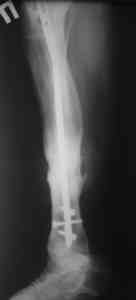

Пример (пациент 46 лет, лечился у нас 4 года назад, внутренний остеосинтез выполнен с определенными погрешностями, но перелом сросся и рецидива инфекции не было): рис. 1,2 - при переводе к нам в институт, рис. 3 - после микрохирругической пластики, рис. 4, 5 - после интрамедуллярного остеосинтеза, рис. 6, 7, 8 - внешний вид и рентгенограммы после окончания лечения